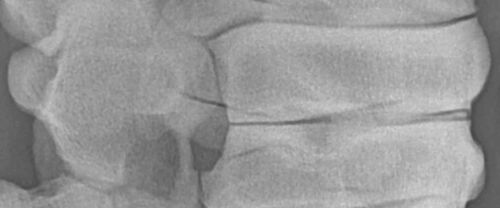

Röntgenaufnahme einer Pferdewirbelsäule

Röntgen

Mobile und stationäre Röntgengeräte der neuesten Generation ermöglichen uns eine umfassende Diagnostik in der Klinik und bei Ihnen vor Ort im heimischen Stall.